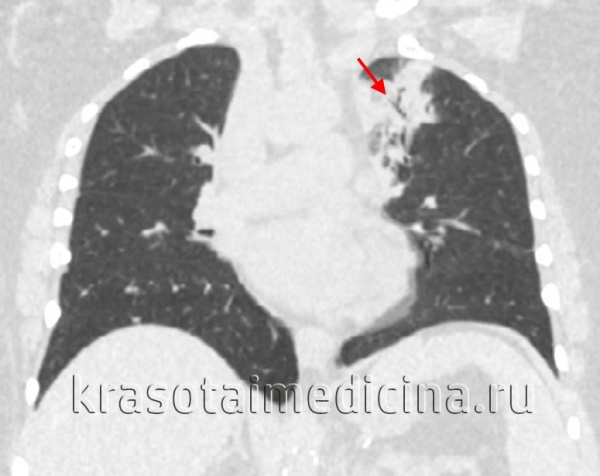

- Рентгенография легких. Рентгенограммы при пневмонии обычно делают в начале заболевания и спустя 3-4 недели для контроля разрешения воспаления и исключения другой патологии (чаще бронхогенного рака легких). При любых видах пневмоний чаще процесс захватывает нижние доли легкого. На рентгенограммах при пневмонии могут выявляться следующие изменения: паренхиматозные (очаговые или диффузные затемнения различной локализации и протяженности); интерстициальные (легочный рисунок усилен за счет периваскулярной и перибронхиальной инфильтрации).

КТ ОГК. Участок пневмонической инфильтрации в верхней доле левого легкого.